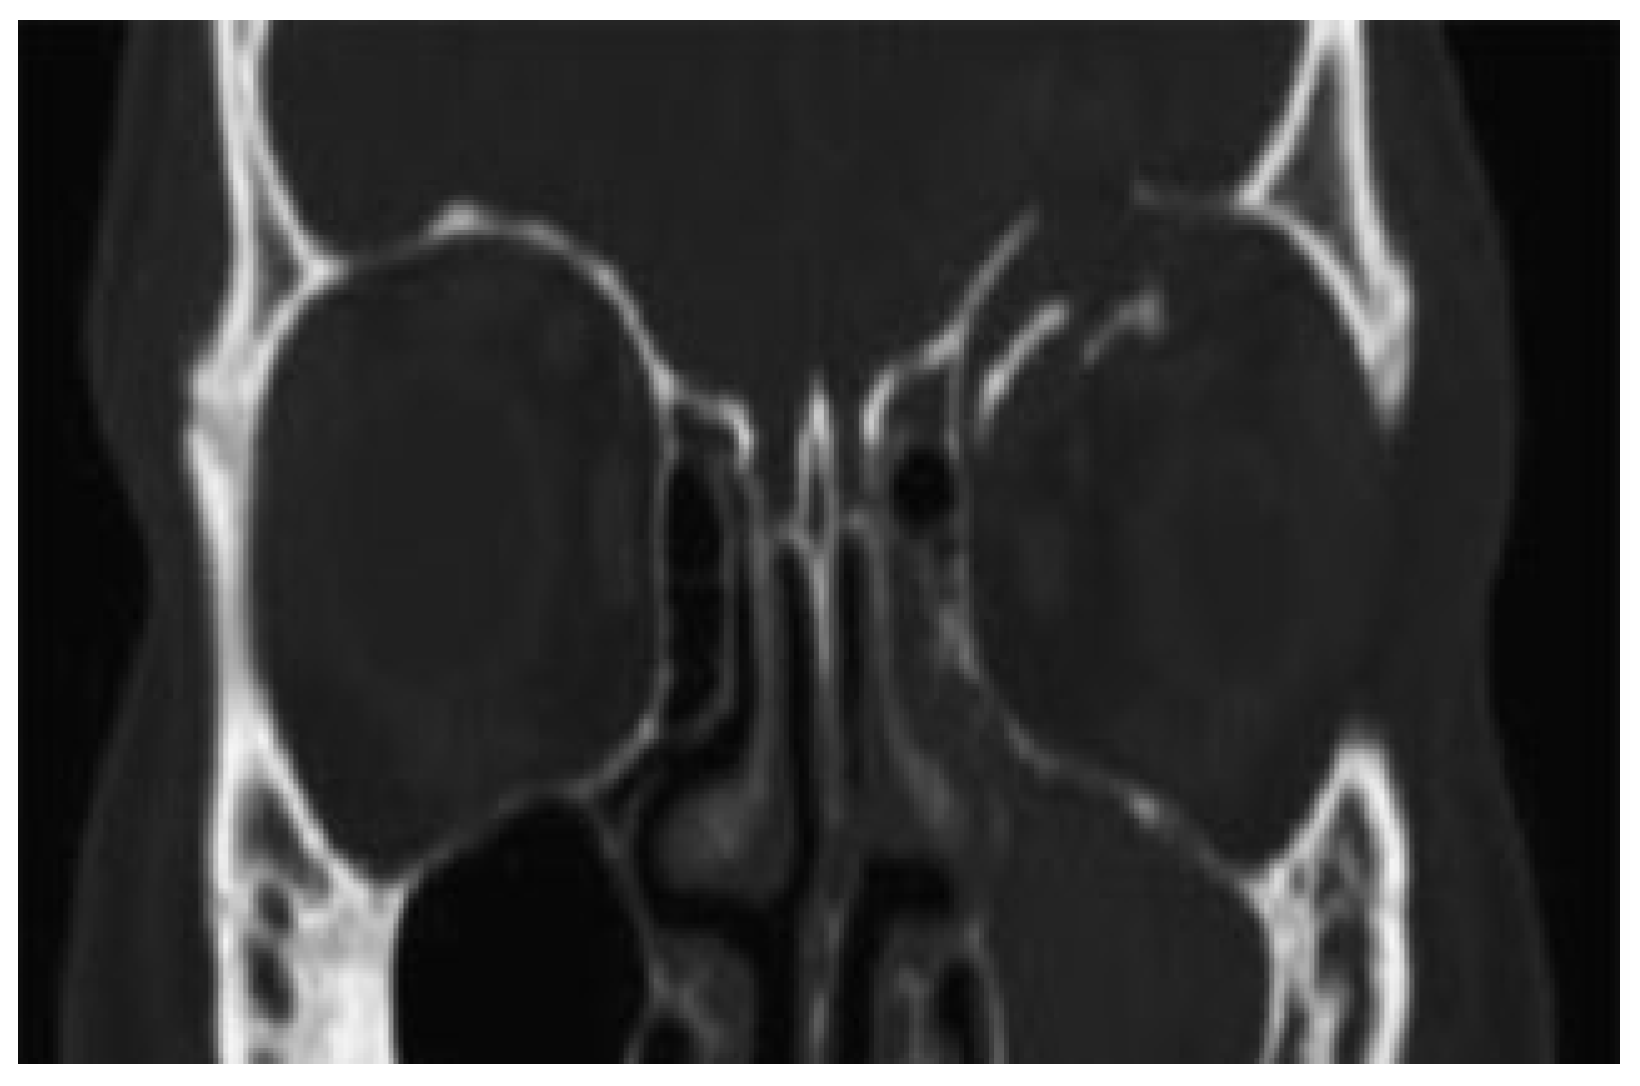

During follow-up, 2 weeks, 2.5, 9 months, and 1 year following the trauma, there were no functional or esthetic problems. CT scan obtained 1 year after trauma showed complete reposition of the left orbital roof fracture (

Figure 3 and

Figure 4).